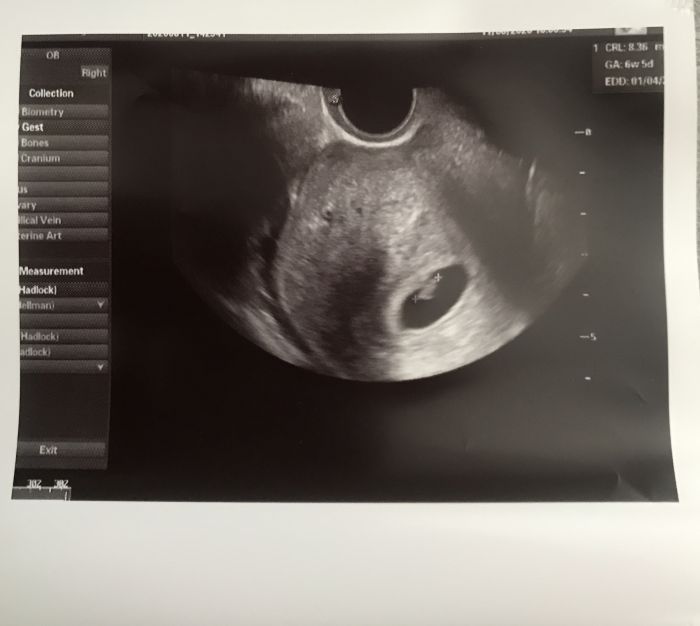

Ano taky baštím listovku, a k tomu fertipronu. Už od te doby co jsme se zacli snažit. Dneska první kontrola, už bylo i srdíčko ❤️ Dnes 6+5 a za 14 dni první poradna ?

Ahoj holky, ráda bych se k vám připojila kdyby to nevadilo. Vypadáte na fajn skupinku. Už bych měla patřit k březnu 20, termín od 24.brezna do 5. dubna. Nyní jsem 7+6 tt. Dnes jsem byla na ko, srdíčko v pořádku. Doma mám 19 mes chlapečka, kterého jsem skoro 3tydny přenášela tak jsem zvědavá nyní. A podařilo se nám na první měsíc snažení.